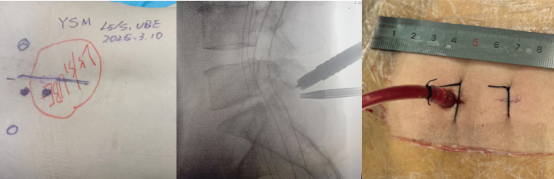

术前影像资料显示L5/S1巨大脱出椎间盘并向近端高度游离

患者阳某某,女,50岁,因反复腰部疼痛7年加重,并右下肢疼痛麻木半月到新利备用网就诊。骨科二区主任陈轼接诊了患者,门诊MRI检查发现阳女士为典型L5/S1巨大椎间盘脱出并压迫神经根,保守治疗无效,建议手术治疗。苗惊雷教授与县医院骨科二区专家团队为阳女士量身定制了无需内固定、创伤更小的UBE微创手术方案。术中通过两个7mm的切口,精准摘除脱出髓核,彻底解除神经压迫。术后次日,阳女士下肢症状显著缓解,已可自主下床活动。

术中图片显示,切口7mm,仅需缝合1针